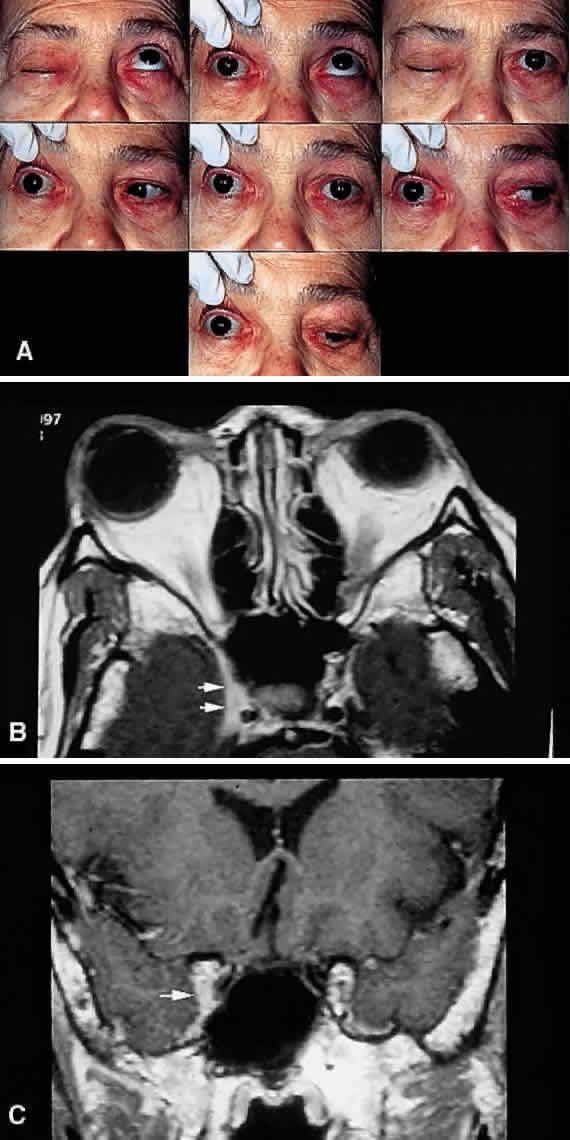

Fig. 15. Parasellar syndrome. A. Composite photograph of an elderly patient with periorbital pain in the distribution of the right supraorbital nerve along with complete ptosis and absent levator function (upper left and upper right). When the eyelid was lifted, she complained of diplopia (center). Note the complete external ophthalmoplegia (remaining panels). MRI revealed a mass eroding the anterior clinoid process and extending into the CS and surrounding brain parenchyma. Given the bony erosion, a diagnosis of Tolosa-Hunt would be inappropriate in this case. A transorbital craniotomy for biopsy revealed metastatic adenocarcinoma. A systemic workup failed to reveal a primary site of involvement. The patient' orbital signs responded to radiation therapy. B and C. Axial and coronal MRI of a different patient who presented in an identical fashion. Note the enlargement of the right CS (arrows). Systemic workup was negative, and the patient responded rapidly to intravenous corticosteroids. The lesion disappeared on subsequent scans with no evidence of recurrence after 2 years. A diagnosis of “presumed Tolosa-Hunt syndrome”is acceptable in this case.